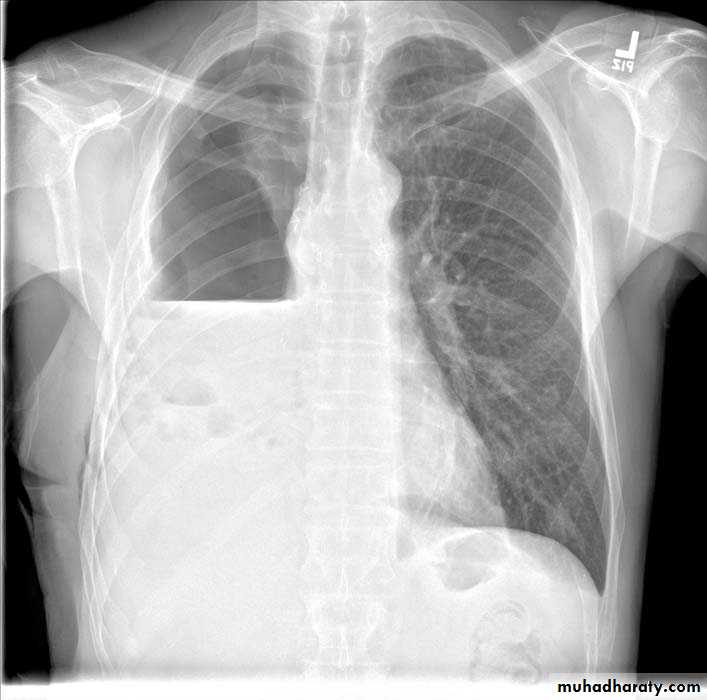

48.opasified hemi thorax Total collapse

Homogenus opacity of the right hemithorax with shifting of the trachea to the same side48.opasified hemi thorax Total consolidation

Homogenus opacity of the left hemithorax with central trachea

Total collapse

Homogenus opacity of the left hemithorax with shifting of the trachea to the same sidePleural effusion

Homogenus opacity of right lower zone with meniscus signOblitration of right cardiophrenic and costophrenic angles

Homogenus opacity of the right hemithorax

Oblitration of cardiophrenic and costophrenic angles

Shifting of the trachea to the opposite side

Pleural effusion

Homogenus opacity of right lower lobe with Oblitration of right cardiophrenic and costophrenic angles.

Meniscus sign